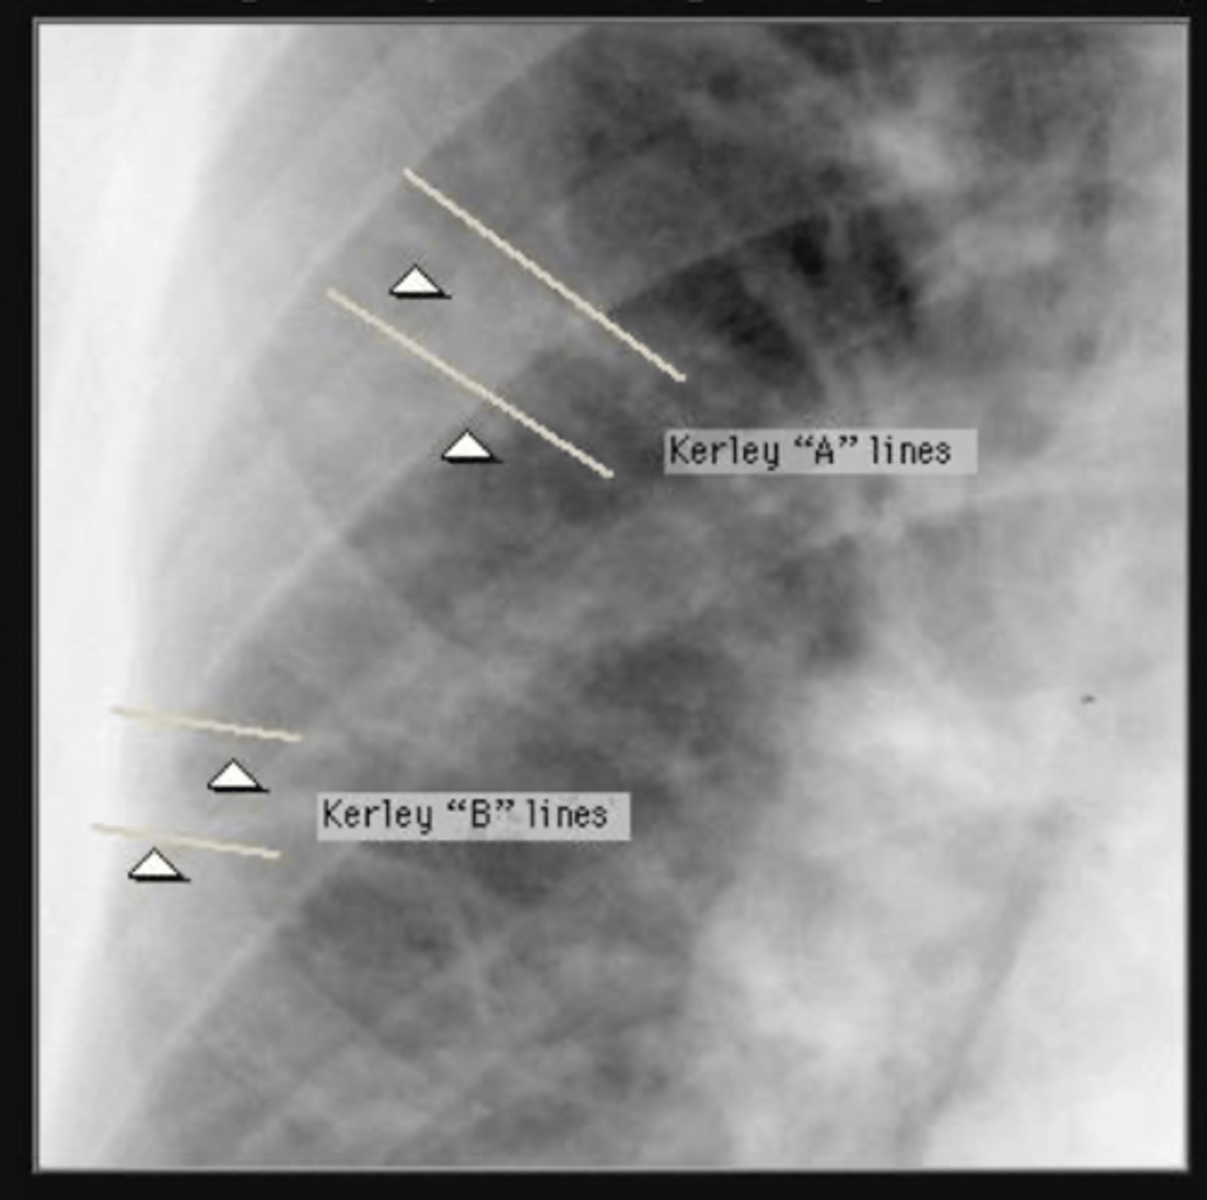

What finding indicates pulm edema in CHF?

kerley a and B lines

<p>kerley a and B lines</p>

Moderate - Kerley B lines in lateral basilar regions